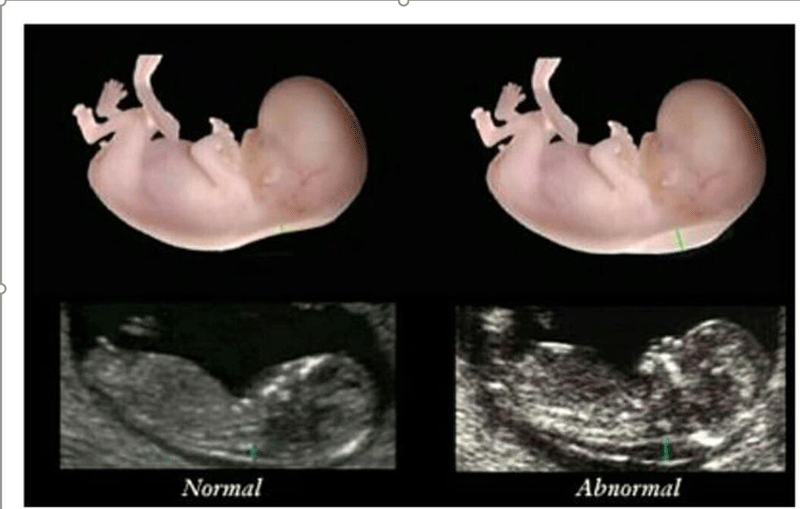

nt是胎儿颈后透明袋的简称,全称为(nuchal teanslucency),nt检查就是胎儿颈后透明带检查,检查胎儿颈后部皮下组织内液体积聚的厚度。

nt检查的主要作用就是获得nt值,通过nt值诊断胎儿是否正常,是否有染色体疾病和其他原因造成胎儿畸形,如果通过nt值提示胎儿有异常,在做四维彩超和唐氏筛查的时候将会重点关注。

nt检查正常值

nt检查正常值一般是在≤2.5mm,只要通过nt检查发现nt值在正常值范围内,就可不用担心了,nt检查属于一次检查。

nt值异常原因

1、通过nt检查,nt值增厚的原因可能是因为测量错误、测量误差等原因造成;

2、如果没有测量误差,就是真正病理上的问题,就是胎儿染色体异常、胎儿大动脉畸形、胎儿静脉导管血流异常或者是淋巴系统排泄失常等原因,